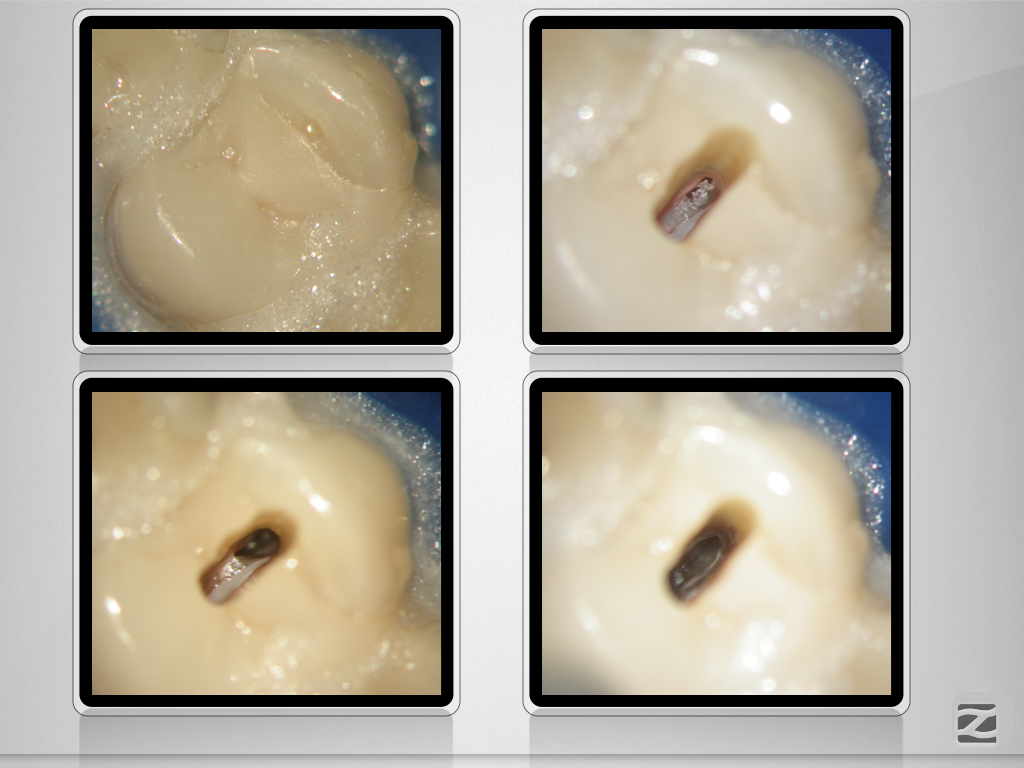

15D.006

Wie weit ist weit genug?